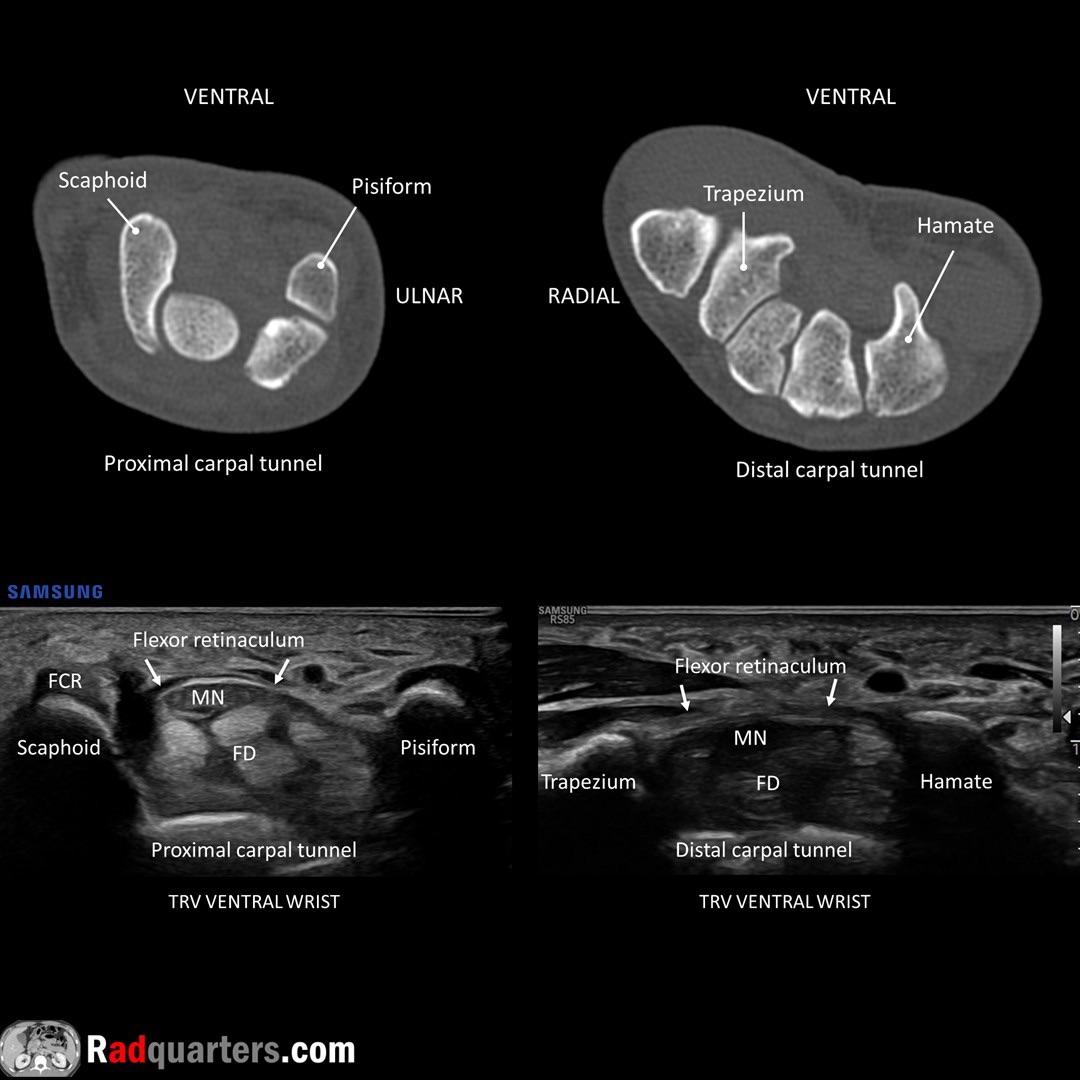

From www.reddit.com

CT & ultrasound anatomy of the carpal tunnel r/Radiology Is Ultrasound Good For Carpal Tunnel Therapeutic ultrasound as independent or adjunct therapy in treating carpal tunnel syndrome (cts). The minimally invasive treatment, which uses a thread to. The first randomised controlled trial (rct) to. Results suggest there are satisfying short to medium term effects due to ultrasound treatment in patients with mild to moderate. Carpal tunnel syndrome (cts) is the most common entrapment neuropathy, affecting. Is Ultrasound Good For Carpal Tunnel.